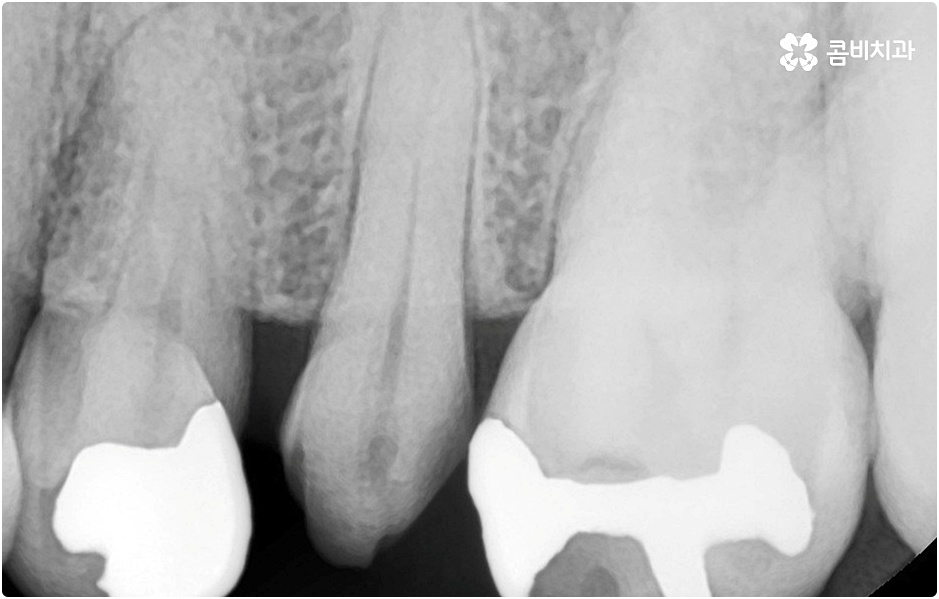

임플란트 시술을 받을 때 치아를 상실한 원인이 무엇인지, 상실하고 나서 그대로 둔 시간이 얼마나 되는지, 현재 치아나 잇몸 등 구강 내부 상황이 어떤지 등등을 먼저 꼼꼼하게 파악할 필요가 있는데요. 예를 들어 20대임플란트 를 받게 된 원인이 사고와 같은 외부 충격으로 인한 것이고 시간이 많이 흐르지 않은데다 다른 구강 질환 (충치나 치주 질환) 이 크게 문제가 되지 않는 상황이라면 젊은 나이이기 때문에 바탕이 되는 잇몸뼈 건강이 비교적 양호할 것이라고 예상할 수 있으며 이런 경우 즉시 임플란트 방식을 검토해 볼 수 있어요. 면밀한 정밀 검사 후 가능하다는 의료진의 진단이 내려진다면 당일에 인공 치근을 심고 임시 크라운까지 올려 바로 사용할 수 있는 즉시 임플란트 방식을 통해 보다 빠르고 간편하게 수복을 할 수 있습니다.

그러나 나이가 젊다고 해도 만약 치아를 상실한 원인이 심각한 구강 질환으로 인한 것이거나 치아를 잃고 나서 오랜 시간 방치를 하였거나 평상시에 당뇨 또는 고혈압 등을 앓고 있었다면 환자분의 잇몸뼈 건강이 양호하지 않을 수 있으며 그런 경우에는 즉시 임플란트 시술을 받을 수 없고 먼저 뼈이식 과정을 통해서 잇몸뼈를 보충해 준 다음 20대임플란트 식립을 진행하는 것이 정확도와 지속성을 높여주는 방법이라고 할 수 있어요.

그러나 언급했던 것처럼 잇몸뼈 상태에 대해서 먼저 체크해 봐야 하기 때문에 누구나 받을 수 있는 치료 과정은 아니라는 점을 분명히 알아두실 필요가 있습니다. 이렇게 잇몸뼈를 보충해야 하는 상황 뿐 아니라 충치 또는 치주 질환을 먼저 깨끗하게 치료해야 하는 상황, 상악동까지의 거리가 너무 짧아서 거상술을 통해 혹시 모를 천공과 염증을 방지해야 하는 상황 등 여러 가지 선치료가 필요한 케이스들이 있을 수 있기 때문에 먼저 환자분들의 상황을 자세하게 파악하기 위해서 꼼꼼한 검진을 해 볼 필요가 있으므로 3D CT 등 정밀 검진 장비 보유 여부가 필수적이라고 말씀드린 거예요.